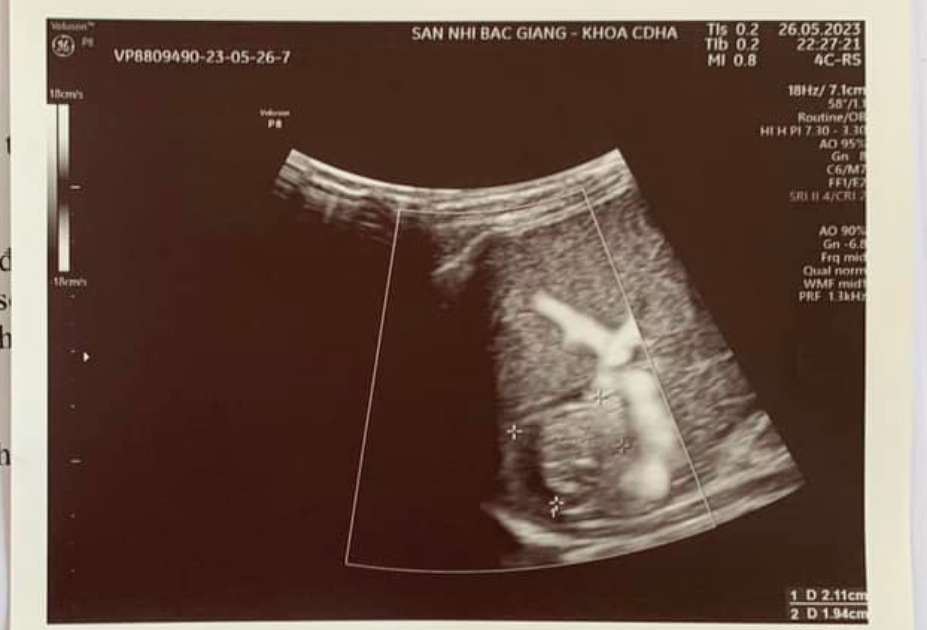

Kết quả siêu âm ổ bụng phát hiện có nhiều dịch tự do ổ bụng và hình ảnh đường vỡ lách khá rõ. Với chẩn đoán trẻ bị vỡ lách trong chấn thương bụng kín, các bác sĩ Khoa Ngoại đã chỉ định làm các xét nghiệm cấp cứu, chuyển bệnh nhi lên phòng phẫu thuật và sẵn sàng truyền máu trong khi mổ.